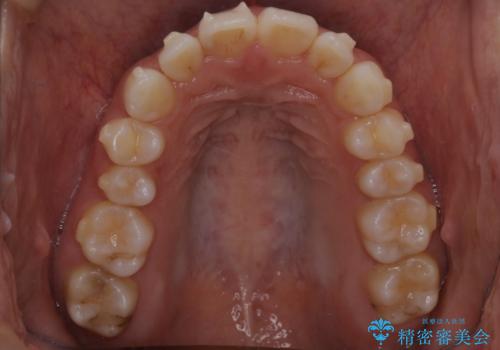

【インビザライン】前歯の後戻りを再矯正

- 前歯が出ていることを主訴に来院されました。検査の結果、口元が標準より出ているわけではなかったため今回はIPRと拡大をし、非抜歯で治療を行いました。

非抜歯でも歯軸の向きを改善したことで前歯が下がり、出っ歯に見えてしまうという主訴が改善しました。